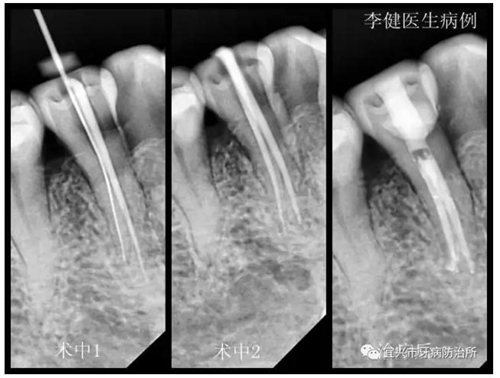

患者,女,55歲,右下前磨牙繼發(fā)齲伴自發(fā)性疼痛前來(lái)就診,X線片顯示為雙根管。術(shù)中1選用鎳鈦根管預(yù)備銼第一次根管預(yù)備未找到,后選用8號(hào)細(xì)銼在根中1/3處找到另一根管,拍X線片確認(rèn)。術(shù)中2再次用鎳鈦根管銼預(yù)備,并用次氯酸鈉溶液反復(fù)沖洗根管。最后利用超聲振蕩機(jī)蕩洗根管后,用熱牙膠系統(tǒng)嚴(yán)密充填根管,并用樹(shù)脂充填窩洞。待后期烤瓷冠修復(fù)。